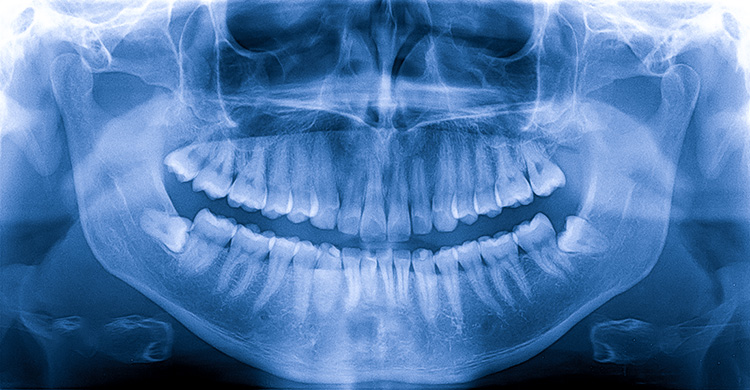

DENTAL X-RAY

X-rays, also known as radiographs, are an essential part of any dental care treatment plan. They are diagnostic, but they can also be preventative, by helping a dentist diagnose potential oral care issues in a patient’s mouth before they become a major problem. An x-ray is a type of energy that passes through soft tissues and is absorbed by dense tissue. Teeth and bone are very dense, so they absorb X-rays, while X-rays pass more easily through gums and cheeks.

• Orthopantomogram (OPG)